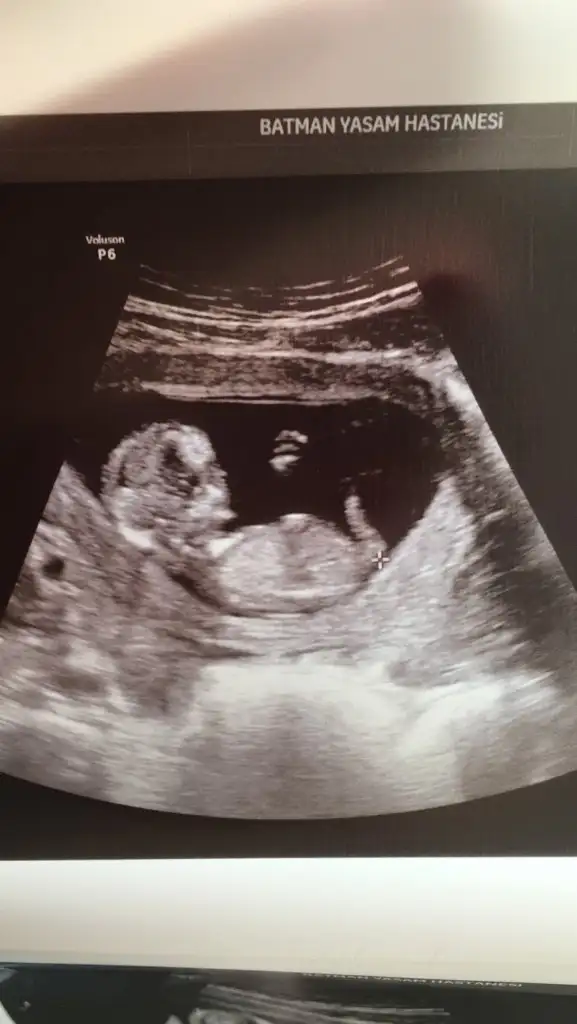

Bizim içinde yorum yapabilir misiniz 12+4 🥰 karından ultrason resimleri bunlar